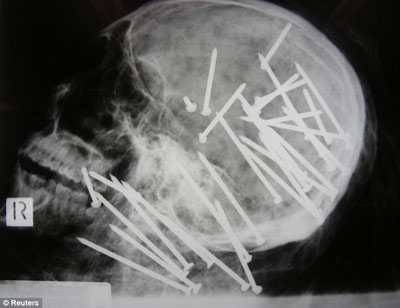

X光显示,刘晨(音译)头部和颈部被钉有30枚钢钉

据报道,该男子名叫刘晨(音译),于2000年移民澳大利亚墨尔本市,4年后搬往悉尼。2008年11月,刘晨的男性友人向悉尼警方报案,称其已经失踪一段时间,警方遂展开调查。两周后,两名在悉尼乔治河上划船的男孩发现了刘晨已经高度腐烂的浮尸。警方称,当时刘晨被一条毯子紧裹着,四肢被电线捆得结结实实,警方将尸体交与法医进行X光检查后惊异地在他头部和颈部发现了30枚钢钉。

负责本案的警官马克·纽汉表示:“尸检结果显示,凶手用一种无绳气动式射钉枪对着死者的头部和颈部开了30枪,这种标准式射钉枪哪都可以买到。”悉尼警司杰夫·贝雷斯福德告诉记者:“这起谋杀案令所有的警察震惊不已,在我36年的办案生涯中,还从来没见过性质如此恶劣的凶案……就是因为这起谋杀案是如此的残忍,所以我们希望公众能够为警方提供更多的破案线索。”